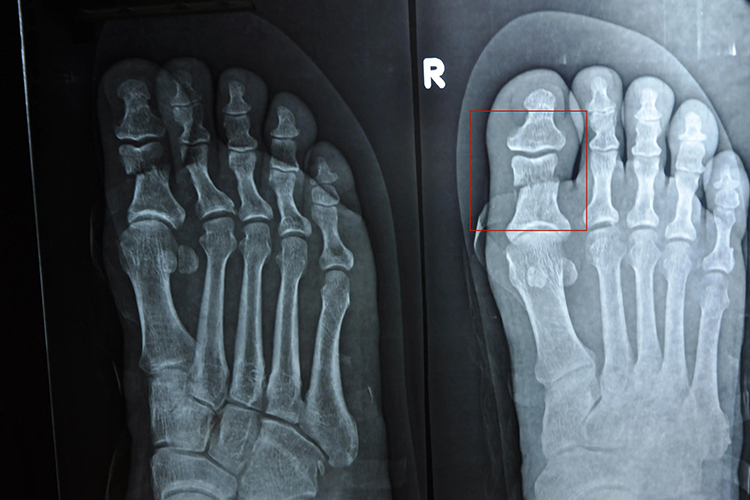

2.骨折类型:骨折的严重程度和类型直接影响愈合时间。单纯性骨折(如裂纹骨折)通常愈合较快,而粉碎性骨折或伴有明显移位的骨折则愈合较慢。粉碎性骨折由于骨折断端多,血液供应差,愈合过程更为复杂,可能需要更长的时间。